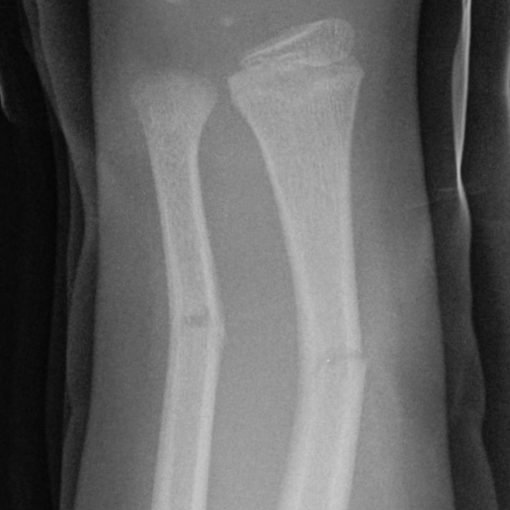

Le radiografie sono utilizzate soprattutto per avere immagini delle ossa.

In genere, le radiografie sono richieste se il medico sospetta una frattura o, meno comunemente, un tumore osseo o un’infezione, oppure per cercare alterazioni che confermino che un soggetto soffre di una certa forma di artrite.